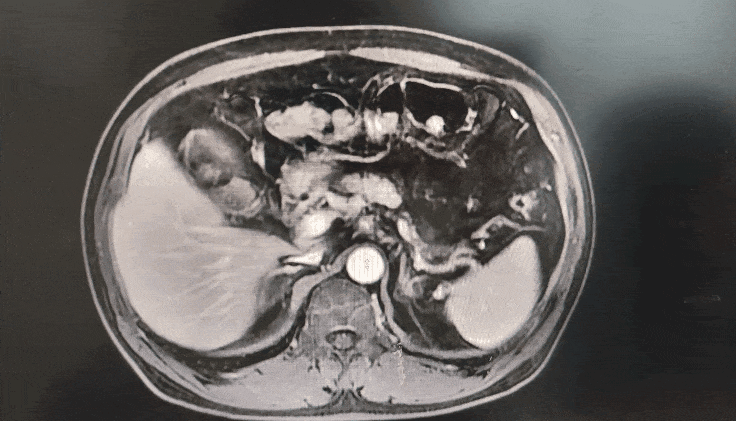

◈ 2022-8-10 胸腹盆增强CT提示:胰腺体部强化减低并胰管局限性稍扩张,肠系膜上动脉、腹腔干近段及局部分支软组织影包绕,考虑患者胰腺占位诊断明确(占位大小无法准确评估),但需鉴别恶性肿瘤及免疫相关疾病。

2022-8-10 胸腹盆增强CT